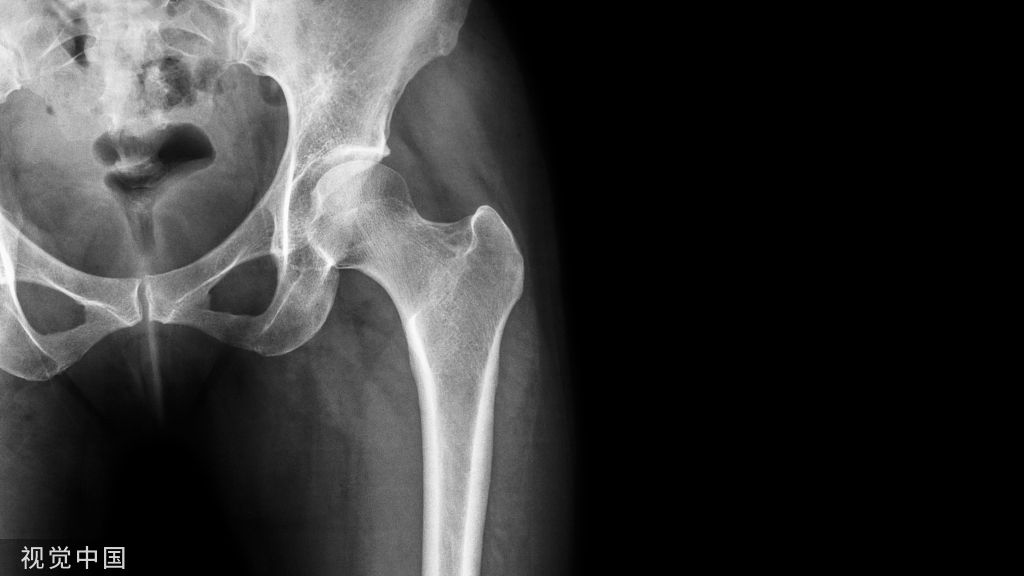

骨质疏松症(OP)是一种以骨量低、骨组织微结构损坏为表现,致骨脆性增加、易发生骨折为特征的全身性代谢性骨病,其可发生于任何年龄,但多见于绝经后女性和老年男性。